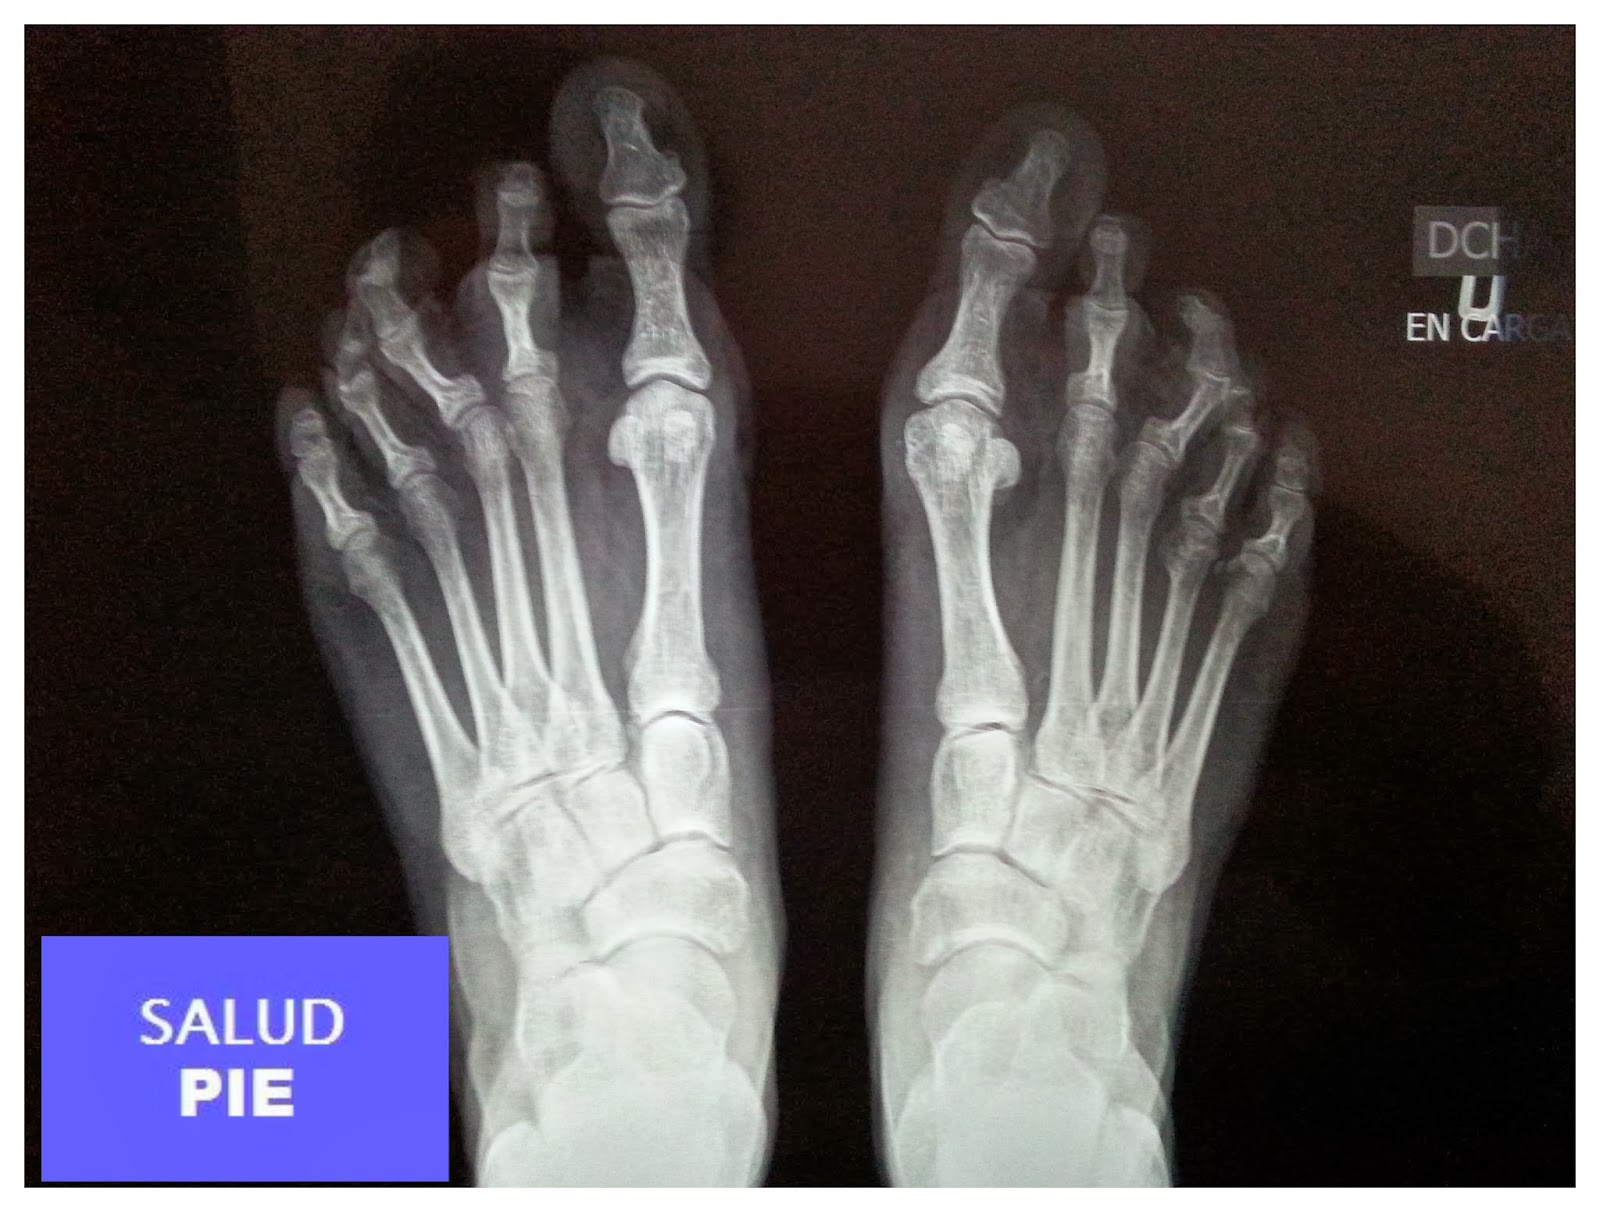

Radiografia De Pie En Carga, Anatomía Radiológica - Radiología Convencional: Pie., 15.4 MB, 11:13, 9,561, Radiología, 2020-09-06T07:30:02.000000Z, 3, Pie cavo - Biclinic, biclinic.com, 960 x 560, jpeg, WebAdemás de la evaluación clínica, es de gran importancia la evaluación radiográfica de los pies en carga en dos proyecciones (anteroposterior y lateral). El examen realizado en. WebEn los últimos 30 años ha habido muchos cambios en el tratamiento quirúrgico del pie plano adquirido del adulto. Actualmente la cirugía con preservación de las articulaciones que. WebLa tomografía axial computarizada (TAC) en carga del pie y el tobillo es una técnica diagnóstica que ha emergido en los últimos años y que se impondrá como una futura., 20, radiografia-de-pie-en-carga, Novedades y Muebles WebAdemás de la evaluación clínica, es de gran importancia la evaluación radiográfica de los pies en carga en dos proyecciones (anteroposterior y lateral). El examen realizado en. WebEn los últimos 30 años ha habido muchos cambios en el tratamiento quirúrgico del pie plano adquirido del adulto. Actualmente la cirugía con preservación de las articulaciones que. WebLa tomografía axial computarizada (TAC) en carga del pie y el tobillo es una técnica diagnóstica que ha emergido en los últimos años y que se impondrá como una futura.

WebUna radiografía de pie puede ayudar a los médicos a encontrar la causa del dolor, la sensibilidad, la hinchazón o una deformidad. Permite ver si hay huesos rotos (fracturas). WebImagen lateral RX pie en carga. Galería . Radiología. Tags. Radiología. Pié. Tobillo. Articulación. Locomotor. Síguenos en las redes sociales Quiénes somos.. WebPDF | On May 1, 2019, David González-Martín published Radiología Pie y Tobillo | Find, read and cite all the research you need on ResearchGate WebPROYECCIONES RADIOLÓGICAS: PIE, DEDOS DEL PIE Y CALCÁNEO ANASTASIYA CHYCHETA, ÁLVARO GÓMEZ, CARLOS PÉREZ Y MARTA VENTURA. WebRadiología simple en traumatología Pie Las proyecciones radiológicas para evaluar traumatismos en el pie incluyen las Rxs de pie AP, oblicua y lateral. Si el dolor lo. WebAl tratarse de una radiografía de 2 proyecciones se obtendrán 2 imágenes. Se le llama pies de cargas porque las radiografías obtenidas son con el pie en posición lateral. En todo. WebLas radiografías del pie en una proyección directa a menudo se realizan para diagnosticar deformidades del pie plano, congénitas o adquiridas. A veces, la.

WebAl tratarse de una radiografía de 2 proyecciones se obtendrán 2 imágenes. Se le llama pies de cargas porque las radiografías obtenidas son con el pie en posición lateral. En todo. WebLas radiografías del pie en una proyección directa a menudo se realizan para diagnosticar deformidades del pie plano, congénitas o adquiridas. A veces, la. WebPaciente en decubito lateral, apoyando la cara lateral del pie sobre el cassete.El haz de rayos es dirigido verticalmente al centro del tarso. Se realiza de forma.